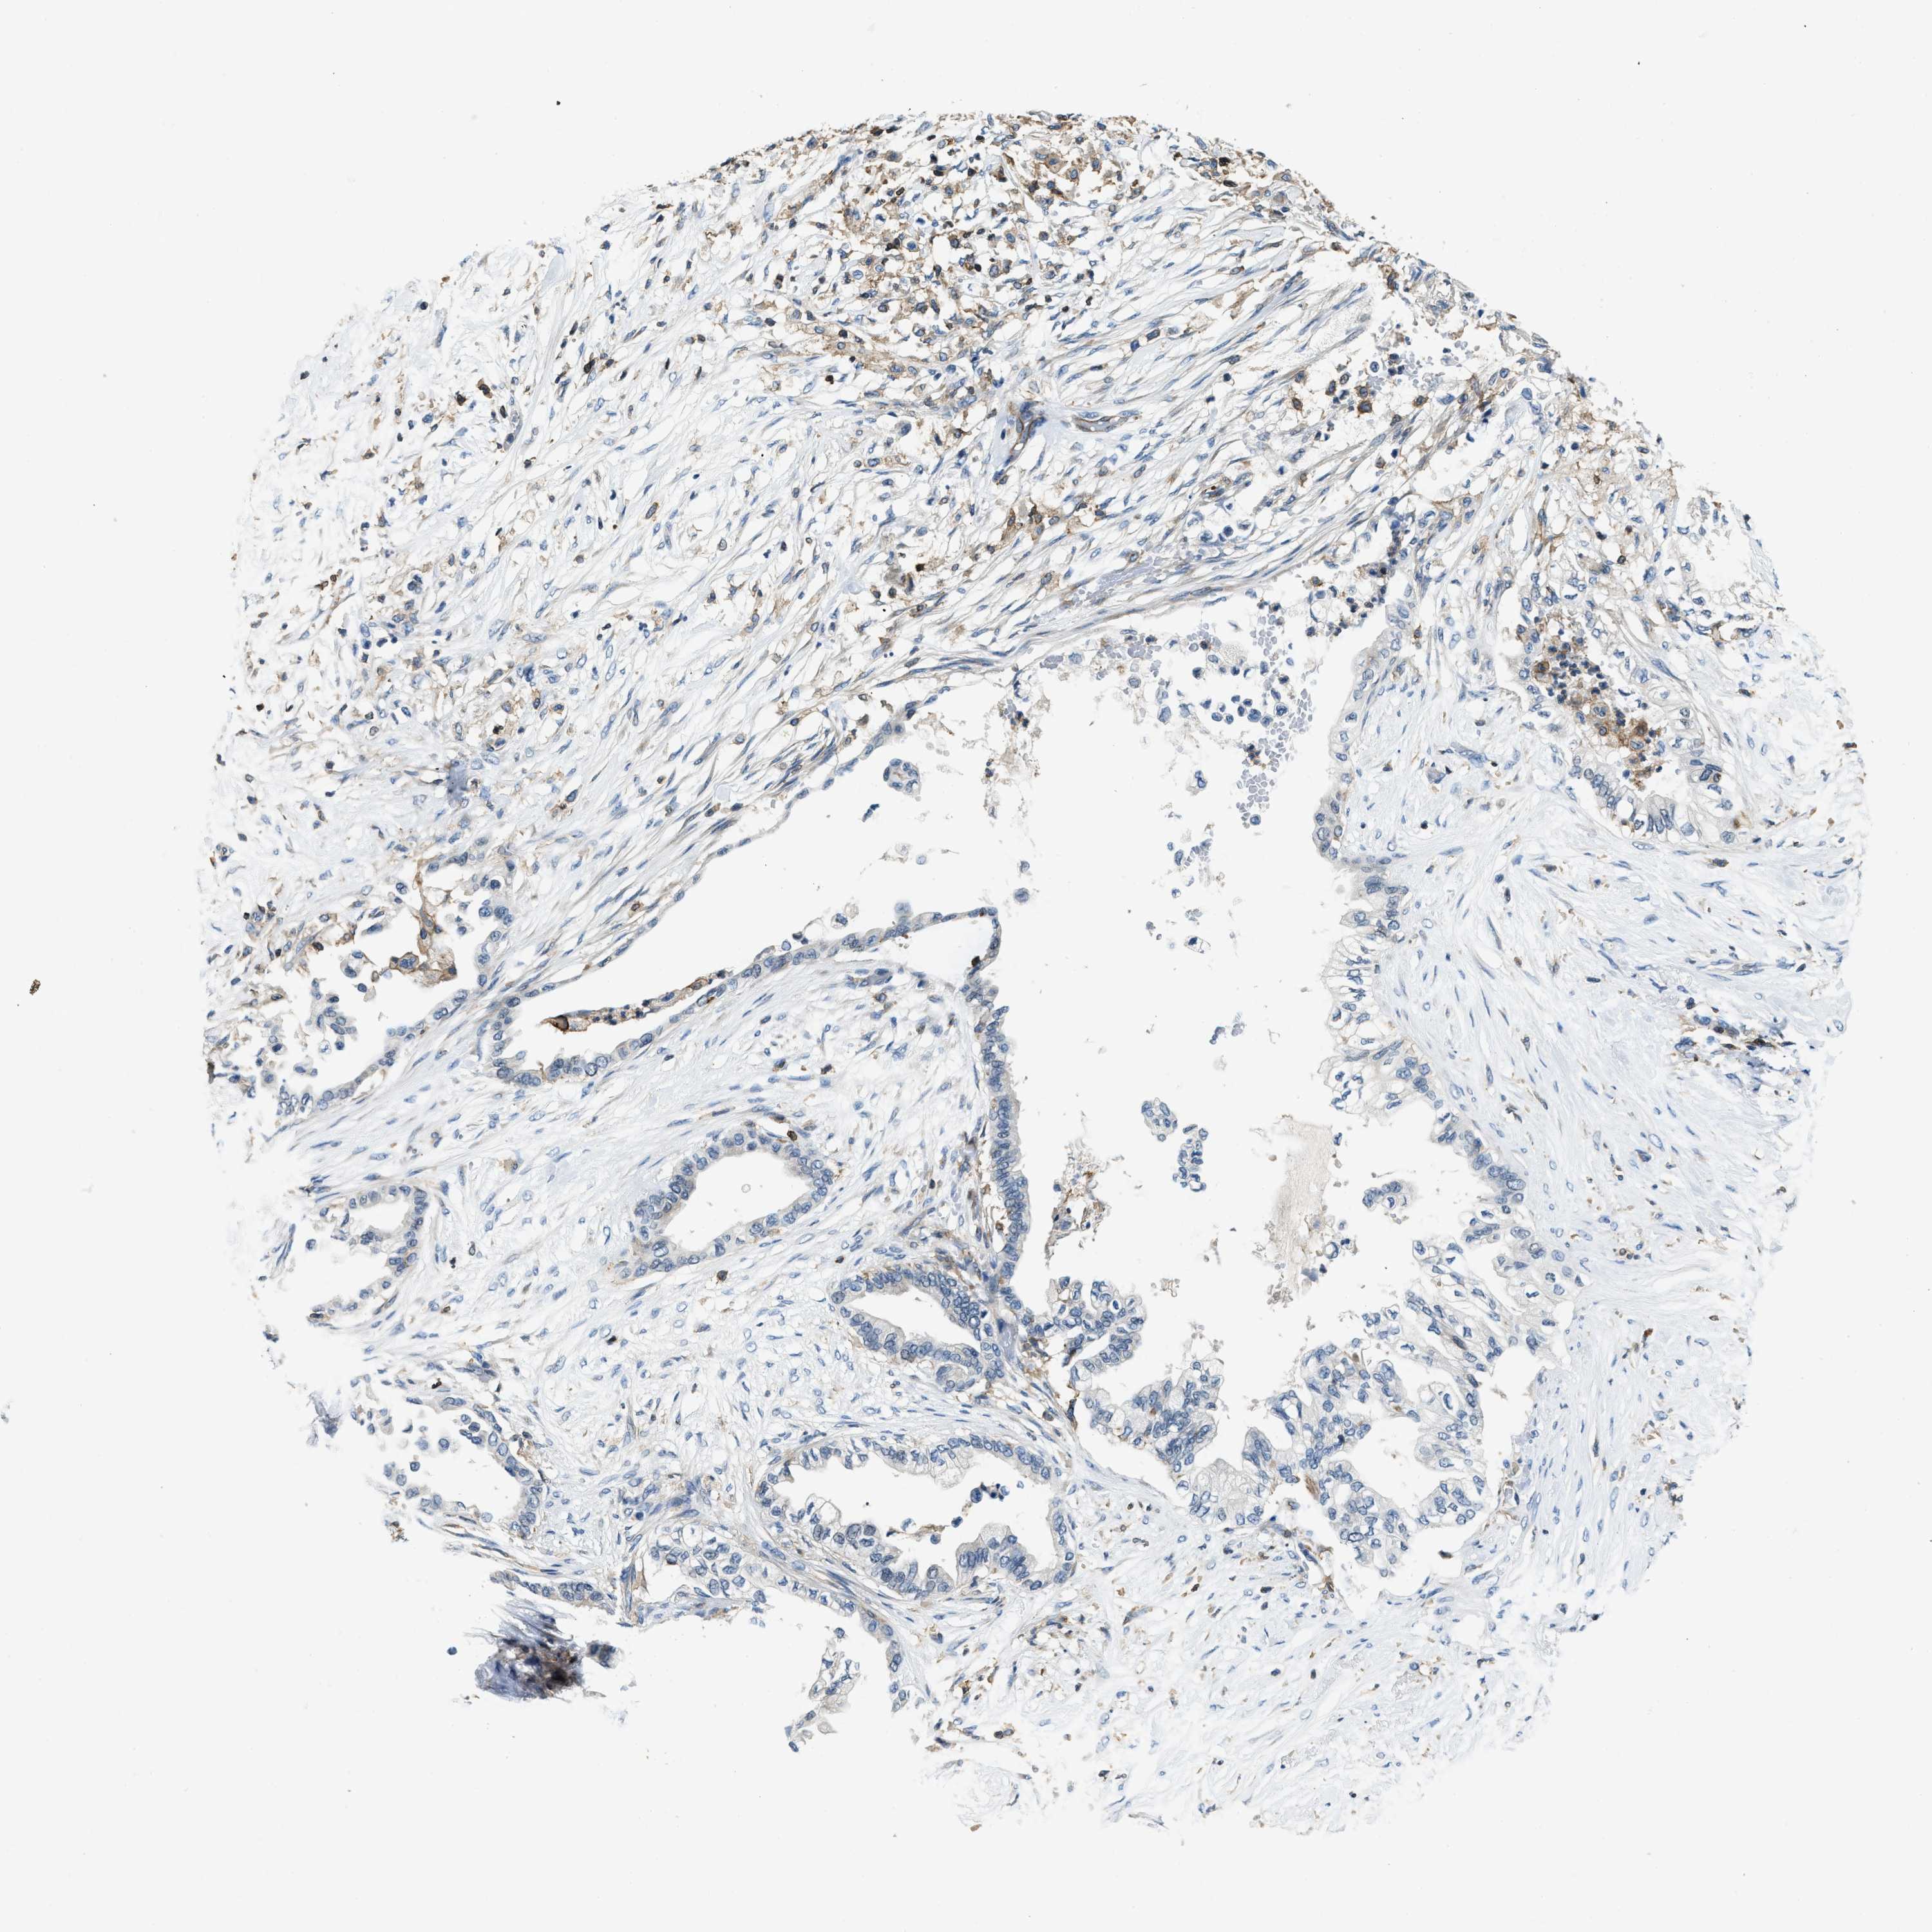

PANCREATIC CANCER - Protein expressioni

A mouse-over function shows sample information and annotation data. Click on an image to view it in a full screen mode. Samples can be filtered based on level of antibody staining by selecting one or several of the following categories: high, medium, low and not detected. The assay and annotation is described here.

Note that samples used for immunohistochemistry by the Human Protein Atlas do not correspond to samples in the TCGA dataset.

Antibody stainingi

Antibody staining in the annotated cell types in the current human tissue is reported as not detected, low, medium, or high, based on conventional immunohistochemistry profiling in selected tissues. This score is based on the combination of the staining intensity and fraction of stained cells.

Each image is clickable and will lead to virtual microscopy that enables deeper exploration of all samples and also displays staining intensity scores, fraction scores and subcellular localization as well as patient and tissue information for each sample.

Antibody HPA021252

Staining

High

Medium

Low

Not detected

Intensity

Strong

Moderate

Weak

Negative

Quantity

>75%

75%-25%

<25%

None

Location

Nuclear

Cytoplasmic/membranous

Cytoplasmic/membranous,nuclear

Adenocarcinoma, NOS